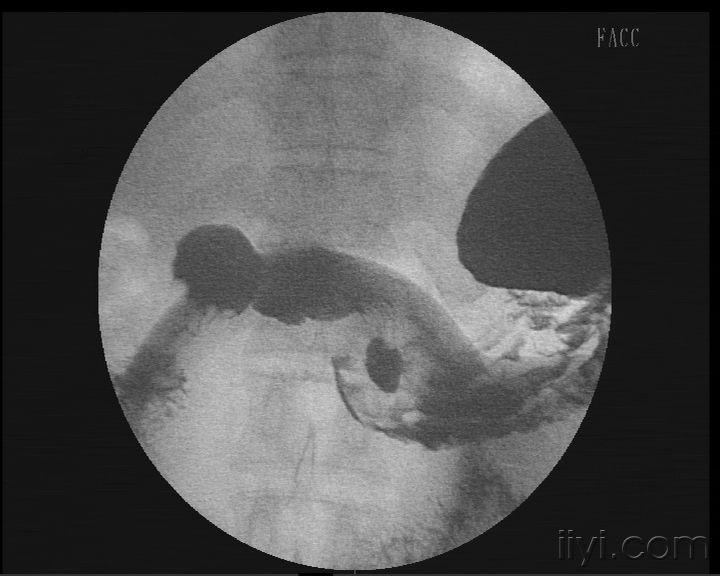

术前上消化道造影显示胃体肿瘤.